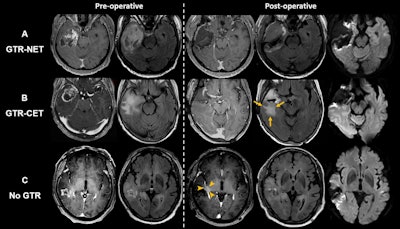

Moon's team categorized patients into the following prognostic groups: Gross total resection of a noncontrast-enhanced tumor; gross total resection of a contrast-enhanced tumor; and no gross total resection.

Axial MRI scans show extent-of-resection groups for (A) gross total resection (GTR) of both contrast-enhanced tumor (CET) and noncontrast-enhanced tumor (NET) (GTR-NET), (B) GTR of CET but NET remained (GTR-CET), and (C) no GTR. Scans show (B) residual T2 and fluid-attenuated inversion recovery (FLAIR) high-signal infiltrative tumor (arrows) and (C) residual CET around the surgical cavity (arrowheads). Diffusion-weighted imaging (right-side column) was used to differentiate residual T2-weighted or FLAIR signal

hyperintensity as a result of NET from cytotoxic surgery-induced changes. Images and caption courtesy of the RSNA.